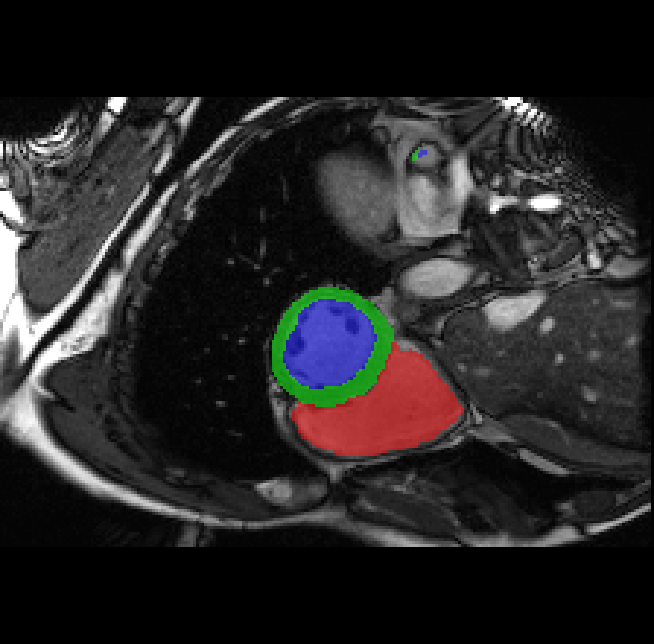

Table 2 presents an ablation study and compares SparseMamba-PCL with nine SOTA scribble-supervised methods across the three datasets. Out method achieves the highest Dice score across all the datasets, and the lowest (CHAOS) and second lowest (ACDC and MSCMRSeg) HD95 values, confirming its effectiveness in segmentation accuracy and boundary refinement. Baseline+SPOBE and Baseline+PCL improve upon the Baseline (SparseMamba), demonstrating the benefits of boundary-aware supervision and SAM-guided learning. Fig. 4 (l) compares the segmentation performance of SparseMamba-PCL with other scribble-supervised methods, showing smoother edges that precisely delineate object boundaries, unlike the jagged or blurred edges in other methods. The examples also demonstrate the consistent segmentation quality achieved by SparseMamba-PCL across ACDC, CHAOS, and MSCMRSeg, highlighting its adaptability across multiple medical domains. This adaptability and precise segmentation is crucial for accurate volumetric analysis and clinical decision-making, where even subtle boundary inaccuracies can lead to diagnostic errors. In summary, the SparseMamba-PCL architecture provides a consistent and robust improvement in segmentation metrics across diverse medical image datasets.

Refer to caption Refer to caption Refer to caption Refer to caption Refer to caption Refer to caption Refer to caption Refer to caption Refer to caption Refer to caption Refer to caption Refer to caption

(a) (b) (c) (d) (e) (f) (g) (h) (i) (j) (k) (l)

Figure 4: Qualitative comparison of weakly-supervised segmentation methods on ACDC, CHAOS, and MSCMRSeg datasets. (a) Input image, (b) ground truth, and segmentation results from (c) USTM [16], (d) Scribble2D5 [5], (e) CycleMix [26], (f) ShapePU [27], (g) S²ME [21], (h) ScribbleVC [12], (i) TDNet [30], (j) PacingPseudo [25], (k) Scribbleformer [13], and (l) SparseMamba-PCL are given.